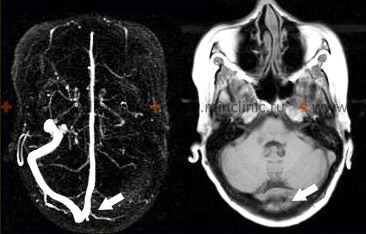

- სისხლძარღვების ვიზუალიზაცია (MRA, CTA, DSA): შეიძლება აჩვენოს დამახასიათებელი ანომალიები, როგორიცაა სეგმენტური შევიწროება ("მძივისებრი/beading"), სტენოზი, ოკლუზიები ან ზოგჯერ ანევრიზმები. თუმცა, მიგნებები შეიძლება იყოს არასპეციფიკური (ბაძავდეს ათეროსკლეროზს ან RCVS-ს) და ვიზუალიზაცია შეიძლება იყოს ნორმალური, განსაკუთრებით წვრილი სისხლძარღვების ვასკულიტის დროს. ციფრული სუბტრაქციული ანგიოგრაფია (DSA) ითვლება ოქროს სტანდარტად სისხლძარღვის მორფოლოგიისთვის, მაგრამ არის ინვაზიური და აქვს რისკები.

მრ ვენოგრაფია აჩვენებს მარცხენა განივი სინუსის თრომბოზს. მიუხედავად იმისა, რომ ვასკულიტმა *შეიძლება* დააზიანოს ვენები/სინუსები, ის ძირითადად აზიანებს არტერიებს. ვენური თრომბოზი არის განსხვავებული მდგომარეობა, რომელსაც ზოგჯერ იწვევს ინფექცია ან ანთება. - თავის ტვინისა და ლეპტომენინგეალური გარსის ბიოფსია: ითვლება საბოლოო სადიაგნოსტიკო ტესტად, განსაკუთრებით საეჭვო PACNS-ის დროს, როდესაც სხვა მიზეზები გამოირიცხება [1, 2]. ბიოფსია, რომელიც აჩვენებს სისხლძარღვების კედლების ტრანსმურალურ ანთებას, ადასტურებს დიაგნოზს [1]. თუმცა, ის ინვაზიურია პოტენციური რისკებით და შედეგი შეიძლება იყოს შეზღუდული დაავადების კეროვანი ბუნების გამო (შერჩევის შეცდომა/sampling error) [1, 2]. ბიოფსია, როგორც წესი, მიზანმიმართულია იმ უბნისკენ, რომელიც მრტ-ზე ანომალიას აჩვენებს [2].